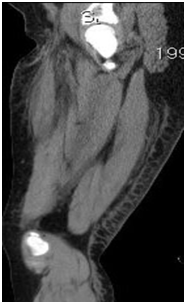

Computed tomography Cross-sectional imaging is Thickening of the skin and the septa in the subcutaneous tissue and occasionally, small fluid collections may be present in the sub dermal areas or superficial to the fascia. In practice: Diagnosed when Doppler is performed to rule out DVT (Figure 2).

Figure 2 Sagittal CT of the thigh shows skin thickening posteriorly with thickened subcutaneous septa.